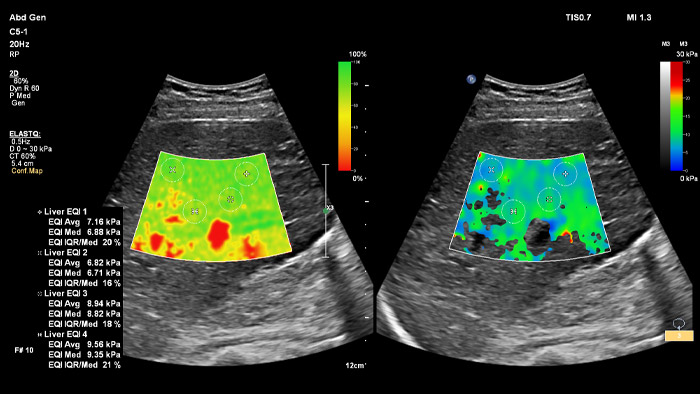

ElastQ provides a 2D shear wave (2D-SWE) real-time assessment of tissue stiffness that is noninvasive, reproducible, and easy to perform. ElastQ also includes the ability to make retrospective measurements on stored images and includes a confidence map for adequate shear wave propagation display.

ElastQ imaging

*Side-by-side view of unique imaging confidence and stiffness maps helps reduce workflow steps and allows for simultaneous map correlation during acquisition and measurement phases.